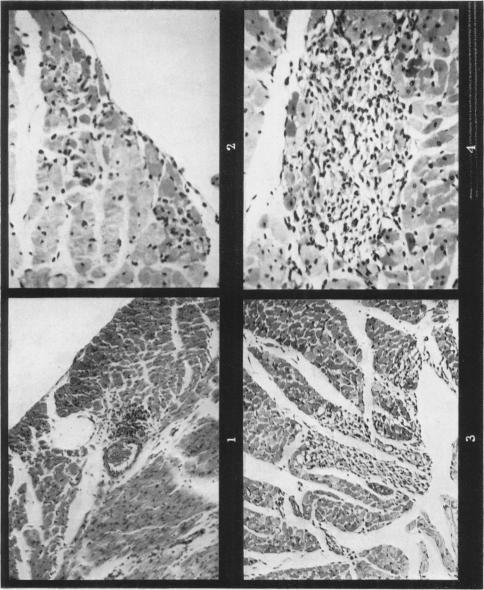

JONES J H

Br J Exp Pathol. 1962 Jun;43(3):257-63.